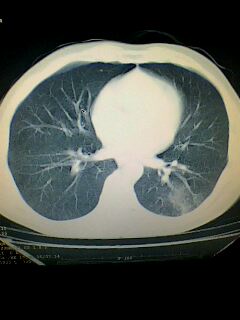

标题: CT28315:咳嗽咳痰咯血半月并胸痛 [打印本页]

标题: CT28315:咳嗽咳痰咯血半月并胸痛

1、纵膈窗效果不好,初步考虑左肺下叶感染性病灶,建议正规抗炎治疗后复查   2、右肺下叶陈旧性病灶伴局部胸膜增厚。

考虑左肺下叶周围型肺癌.图象欠清,请问病人贵更?

考虑左肺下叶周围型肺癌.

左下肺肿块影,深分叶,考虑肺癌。